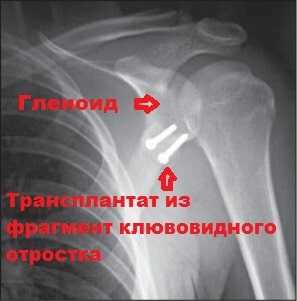

В случае выраженного дефицита костной структуры суставного отростка лопатки выполняем костно-пластическую операцию Латарже по транспозиции клювовидного отростка. Операцию выполняется как открыто — через небольшой разрез кожи 6-8 см по передней поверхности плечевого сустава, так и артроскопически (артроскопическая операция Латарже).

Рисунок: Компьютерная томограмма через 6 мес. после операции и приживления трансплантата.

Реабилитационный период после костно-пластической операции Латарже составляет в от 6 до 12 месяцев, требует выполнения контрольных компьютерных томограмм для подтверждения прирастания трансплантата.

Наиболее частым видом хирургического вмешательства, который применяется для ликвидации нестабильности плечевого сустава, связанной с дефектом кости является операция Латарже (Latarjet).

Во время этой операции производят отсечение клювовидного отростка. Далее фрагмент клювовидного отростка вместе с сухожилием переносится на край гленоида.

Для фиксации клювовидного отростка к краю гленоида используется два винта. Через несколько месяцев клювовидный отросток срастается с лопаткой, а площадь гленоида увеличивается на 20-25 процентов.

Расположенный таким образом костный фрагмент клювовидного отростка вместе с сухожилием двуглавой мышцы ограничивает возможность головки плечевой кости выскальзывать из сустава.

При правильном выполнении операции частота рецидивов после операции крайне невелика.